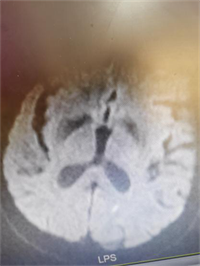

急诊科医师接诊时患者已中度昏迷,鼾式呼吸,小便失禁。立即完善急诊头颅CT提示左侧丘脑及侧脑室旁脑软化灶。头颅MRI提示小脑、两侧枕叶、左侧顶叶急性脑梗死。